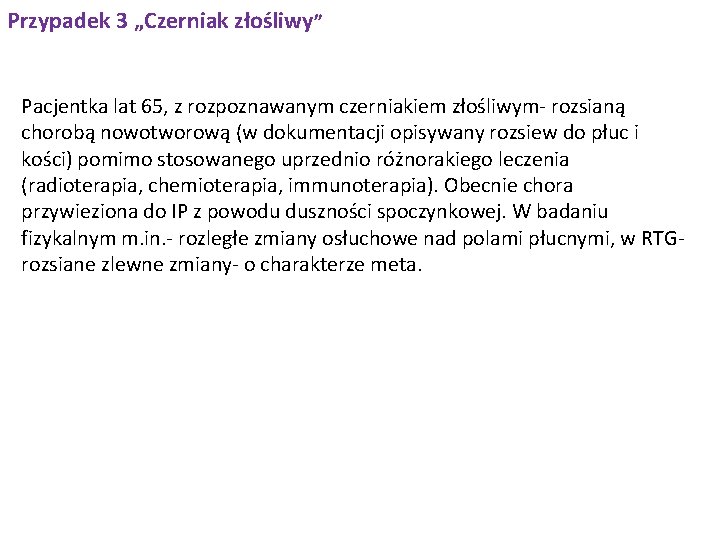

Przypadek 3 „Czerniak złośliwy” Pacjentka lat 65, z rozpoznawanym czerniakiem złośliwym- rozsianą chorobą nowotworową (w dokumentacji opisywany rozsiew do płuc i kości) pomimo stosowanego uprzednio różnorakiego leczenia (radioterapia, chemioterapia, immunoterapia). Obecnie chora przywieziona do IP z powodu duszności spoczynkowej. W badaniu fizykalnym m. in. - rozległe zmiany osłuchowe nad polami płucnymi, w RTG- rozsiane zlewne zmiany- o charakterze meta.

Przypadek 3 Pola płucne z obecnością zlewnych zmian o charakterze meta. Sylwetka serca niepowiększona. Przepona i kąty przeponowo-żebrowe zatarte.